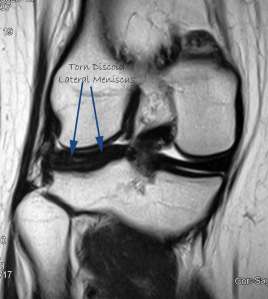

The diagnosis is made with clinical history and examination. Usually an MRI scan is necessary to clinch the diagnosis.

This is my patient who is 18-years-old and she presented with acute locking and pain in the right knee. MRI confirmed a torn discoid lateral meniscus.